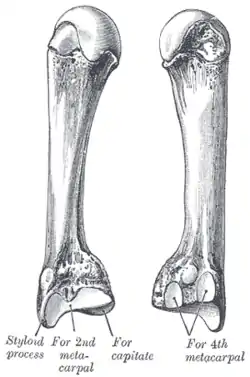

Second metacarpal bone Third metacarpal bone

Third metacarpal bone Carpal boss in plain X-Ray.